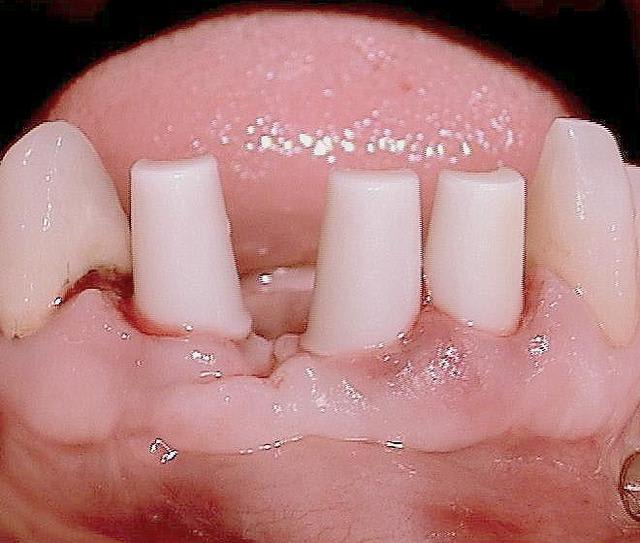

Oui tu as bien raison :-) Ci joint quelques photos en rapport avec ta question ....

Les nombreux cas déjà postés montrent que cela fonctionne et au long terme (radios après 10 ans), et que l implantologie peut être "démystifier" ( si le mot existe...) :-)